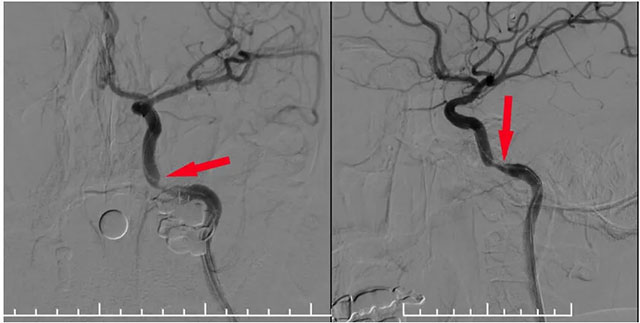

▲ 球囊擴張支架在微導(dǎo)絲導(dǎo)引下到位于狹窄段

▲ 球囊擴張后支架釋放狹窄已明顯改善

術(shù)中,張琪博士在劉春醫(yī)生、周林華醫(yī)生及醫(yī)護團隊協(xié)助下從左側(cè)股動脈穿刺,置入6F導(dǎo)管鞘。將6F導(dǎo)引導(dǎo)管在泥鰍導(dǎo)絲導(dǎo)引下置入左側(cè)頸內(nèi)動脈,造影明確巖骨段狹窄呈,測量狹窄段長度及近遠端血管支架,選擇合適支架,隨后在微導(dǎo)絲輔助下越過狹窄段超選至C6段,選用4.0*18球擴支架,沿微導(dǎo)絲到位狹窄段,球囊擴張至6atm,即刻釋放支架,即刻造影見狹窄明顯改善,支架貼壁良好,血流通暢,狹窄段完全覆蓋。